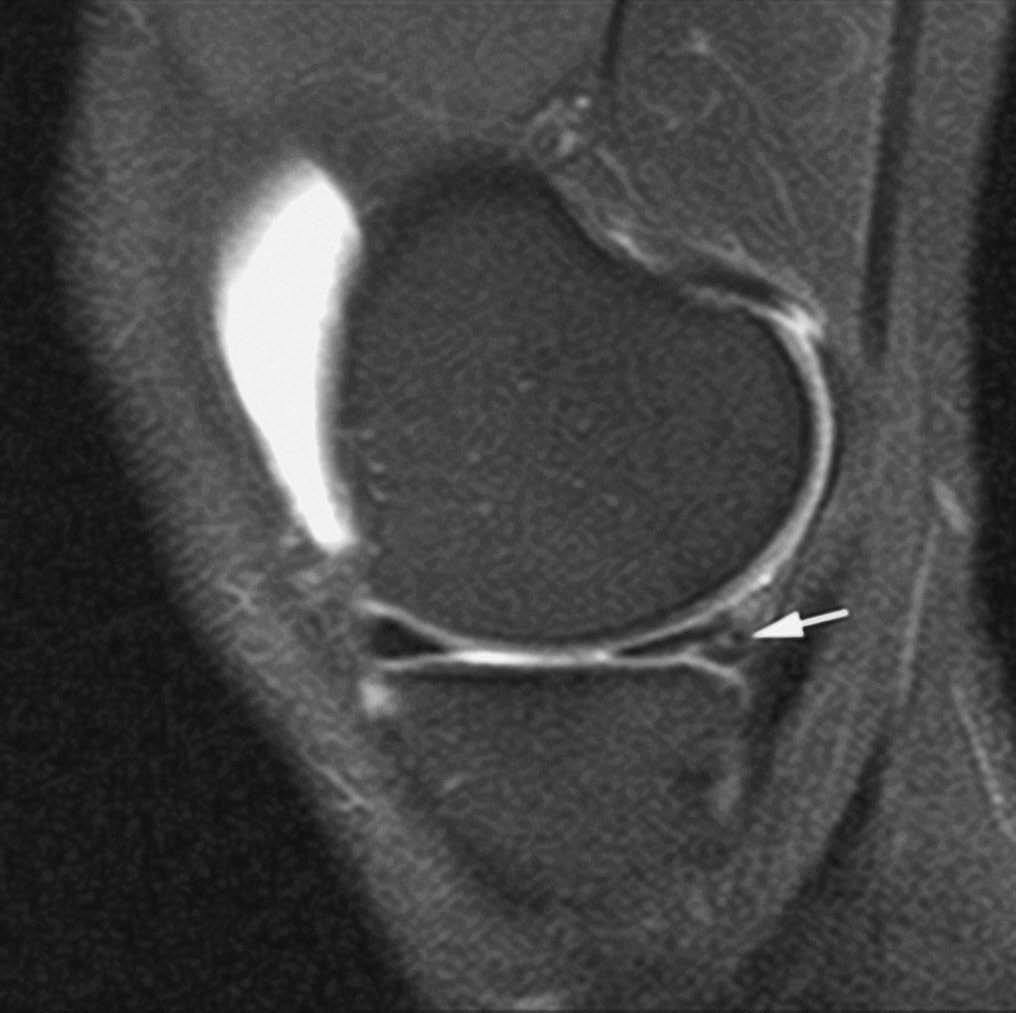

En la actualidad, la RMA es el método más eficaz en la valoración de las lesiones ligamentosas del tobillo. En la fase aguda, su indicación está limitada a aquellos casos en los que el cirujano plantea la realización de una reparación primaria --casos con lesión ligamentosa doble o en deportistas de alta competición--. Sin embargo, su principal indicación es la evaluación de la inestabilidad crónica de tobillo --tiene una sensibilidad del 100% y del 90% para las lesiones crónicas del LPAA y LPC, respectivamente (fig. 9), frente a una sensibilidad del 50% de la RM convencional--20,21.